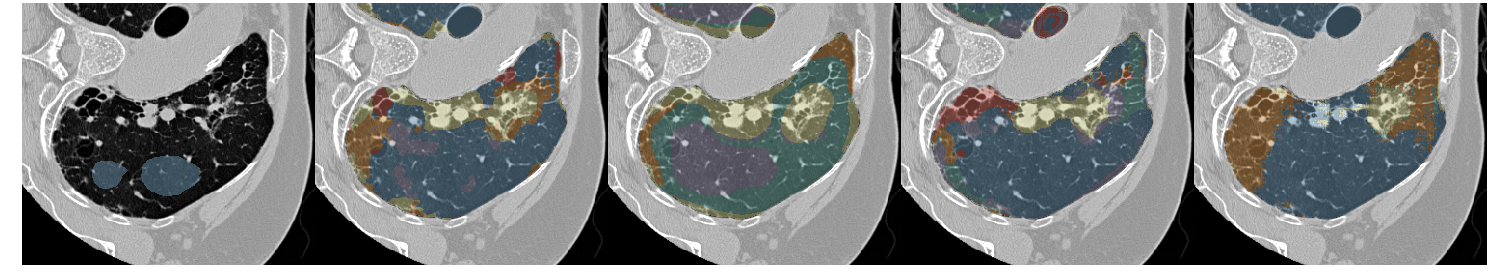

Table III presents a comparison between the proposed network and three previous studies. It has to be noted that all models used the same unsupervised weight (wu=0.1subscript𝑤𝑢0.1w_{u}=0.1) and whenever batch normalization was performed, this was based on batch statistics (instance normalization) since this yielded the best results. Fig. 7 illustrates a few segmentation results for each of the models in Table III.

The first line of the table refers to our previous work [5], which has been converted into a fully convolutional network so it can accept arbitrarily sized images for input. Its low accuracy is probably due to the small receptive field (33×\times33) and the extensive pooling. This architecture was sufficient to describe the local texture of the 32×\times32 single-class patches in [5], but could not capture higher level structure that is present in the whole-lung dataset of this study. The results of the model in Fig. 7 show its noisy output near the lung boundaries or between patterns, where context information could be useful. Segnet [15] and U-net [17] yielded better results, with the latter being slightly faster and substantially more accurate. Both models have a very high number of parameters and large enough receptive fields to capture any relevant information. The superior performance of U-net could be attributed to its skip connections that allow features from the lower scales to directly contribute to its output. Indeed, Fig. 7 illustrates the more detailed results of U-net as opposed to the overly smoothed areas produced by Segnet. Finally, the proposed network yielded the best results, while being faster and having far fewer parameters. The output examples in Fig. 7 indicate that the proposed model manages to keep a better balance between fine details and smooth border among the different classes. Even thought it is really difficult to visually assess the performance of the system for the different classes, there are a few examples in Fig. 7 with wrong classifications on which we can comment. Firstly, parts of the broncho-vascular tree in the third row were recognized as consolidation because of their similar densities, while accentuated terminal bronchial parts, that might be physiological as well, caused the erroneous classification of healthy areas into reticulation, in the first row. Some mistakes however are also attributed in the limited number of annotated classes. For example in row 6, there are emphysematic areas (dark area in the center of the lung) that have been annotated as healthy due to their similar density. Figure 6 shows the confusion matrix of the proposed model. As expected, many of the misclassifications occur between reticulation and honeycombing due to their similar textural appearance. Moreover, healthy tissue is often confused with reticulation probably because of the 2D sections of the bronchovascular tree that could resemble reticular patterns.

Figure 7: Output examples for the models of Table III. From left to right: Ground Truth, ILD-CNN, Segnet, U-net, Proposed. Each example has a different pattern annotated. From top to bottom: Healthy (Blue), Ground Glass Opacity (Purple), Micronodules (Green), Consolidation (Yellow), Reticulation (Orange) and Honeycombing (Red).